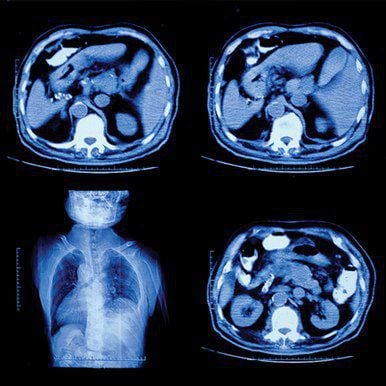

NYU Langone’s Head to Toe Imaging offers an intensive review of essential and cutting-edge imaging techniques in all modalities. Presented by a collaborative team of imagers and clinicians attentive to safety, quality, and economic imperatives, this online CME program emphasizes standardized imaging strategies that support the imperative for clinical decision support.

- Abdominal Imaging

Pearls and Pitfalls of Enterography for Crohn’s Disease – Bari Dane, MD - Updates and Pitfalls for Adrenal Imaging – Myles Taffel, MD